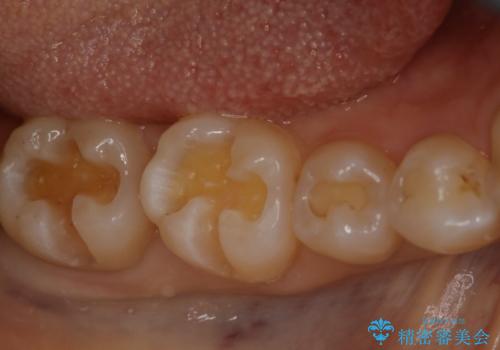

奥歯を綺麗にしたい

- 右下6・7番の咬合面に詰められた保険材料が劣化していたので、審美性・切削量を考慮しセラミックインレー治療を選択しました。

劣化した保険材料・虫歯を全て除去した上で形成しています。